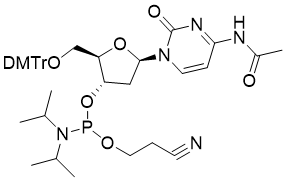

馬鞍山致研生物醫(yī)藥科技有限公司成立于馬鞍山市鄭浦港新區(qū)現(xiàn)代產(chǎn)業(yè)園。公司專(zhuān)注于生物小分子、醫(yī)藥中間體相關(guān)產(chǎn)品的研發(fā)和生產(chǎn),產(chǎn)品主要包括DNA亞磷酰胺單體、RNA亞磷酰胺單體、特殊單體以及按照客戶(hù)要求定制的RNA和DNA,并且公司提供定制合成等方面的研究服...

馬鞍山致研生物醫(yī)藥科技有限公司成立于馬鞍山市鄭浦港新區(qū)現(xiàn)代產(chǎn)業(yè)園。公司專(zhuān)注于生物小分子、醫(yī)藥中間體相關(guān)產(chǎn)品的研發(fā)和生產(chǎn),產(chǎn)品主要包括DNA亞磷酰胺單體、RNA亞磷酰胺單體、特殊單體以及按照客戶(hù)要求定制的RNA和DNA,并且公司提供定制合成等方面的研究服...